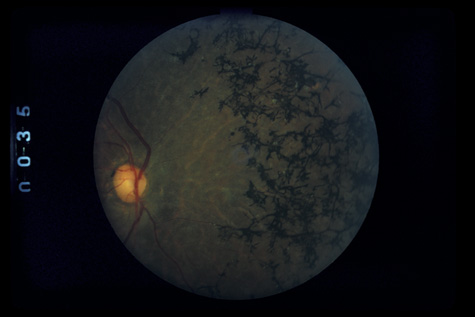

tomography. Eur J Ophthalmol 13:818, 2003 67. Blight R, Hart JCD. Structural changes in the outer retinal layers following blunt mechanical

nonperforating trauma to the globe. An experimental study. Br J Ophthalmol 61:573, 1977 68. Mansour AM, Green WR, Hogge C: Histopathology of commotio retinae. Retina 12:24, 1992 69. Sipperley JO, Quigley HA, Gass JDM: Traumatic retinopathy in primates, the explanation of commotio retinae. Arch Ophthalmol 96:2267, 1978 70. Friberg TR: Traumatic retinal pigment epithelial edema. Am J Ophthalmol 88:18, 1979 71. Bastek JV, Foos RY, Heckenlively J: Traumatic pigmentary retinopathy. Am J Ophthalmol 92:621, 1981 72. Crouch JER, Apple DER: Posttraumatic migration of retinal pigment epithelial melanin. Am J Ophthalmol 78:251, 1974 73. Al-Abdulla NA, Thompson JT, Sjaarda RN: Results of macular hole surgery with and without epiretinal dissection